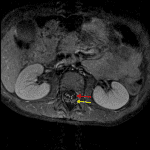

- Diffuse enhancement of nerve roots in the cauda equina, with the ventral nerve roots enhancing slightly more avidly than the dorsal nerve roots

- No associated nodular enhancement or nerve root thickening

- Guillain-Barré syndrome

Diffuse enhancement of nerve roots in the cauda equina, with the ventral nerve roots enhancing slightly more avidly than the dorsal nerve roots. This appearance is concerning for Guillain-Barré syndrome or meningitis. Recommend correlation with CSF analysis. The absence of nodular enhancement makes leptomeningeal neoplastic disease unlikely.